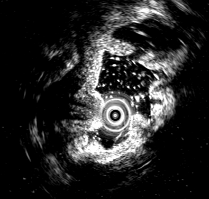

超声内镜清晰显示:胃窦壁内低回声管状肌性组织